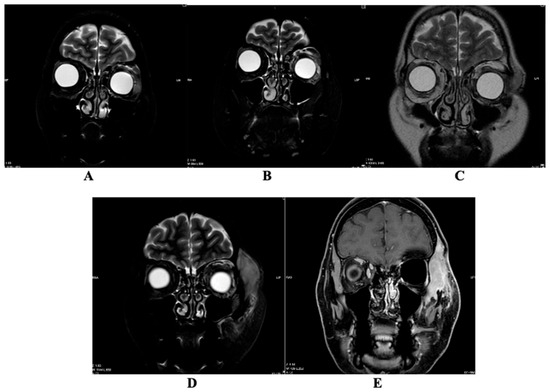

The Complexities of Periorbital Neurofibroma: Diagnostic Ambiguity and Therapeutic Dilemmas: A Case Report and Literature Review

by Marijus Leketas, Gerda Kilinskaitė, Nida Kilinskaitė, Goda Miniauskienė, Žygimantas Petronis and Audra Janovskienė

Diagnostics 2026, 16(5), 732; https://doi.org/10.3390/diagnostics16050732 - 1 Mar 2026

Background: Periorbital tumors represent a diagnostic challenge due to overlapping clinical and histopathological features. Case presentation: We present the case of a 57-year-old female with a recurrent left lower eyelid lesion initially diagnosed as malignant melanoma. Over a seven-year course, the patient underwent [...] Read more.

Background: Periorbital tumors represent a diagnostic challenge due to overlapping clinical and histopathological features. Case presentation: We present the case of a 57-year-old female with a recurrent left lower eyelid lesion initially diagnosed as malignant melanoma. Over a seven-year course, the patient underwent multiple surgical excisions, radiotherapy, systemic therapies, and repeated imaging. Histopathological findings alternated between melanoma, neuroma, hybrid peripheral nerve sheath tumor, and ultimately neurofibroma (NF1). Immunohistochemical staining repeatedly demonstrated positivity for S100 and SOX10, with variable expression of melanocytic markers, underscoring the diagnostic ambiguity between desmoplastic melanoma and NF. Despite multiple interventions, including Pembrolizumab therapy and orbital exenteration, tumor progression persisted. This case highlights the considerable difficulty in distinguishing melanoma from neurofibroma in the periorbital region, particularly when histological and immunohistochemical profiles overlap. Conclusions: Accurate diagnosis requires a multidisciplinary approach, repeated reassessment, and awareness of rare presentations. Our report emphasizes the importance of integrating clinicopathological data and selected molecular diagnostics to optimize management of such complex cases. Full article